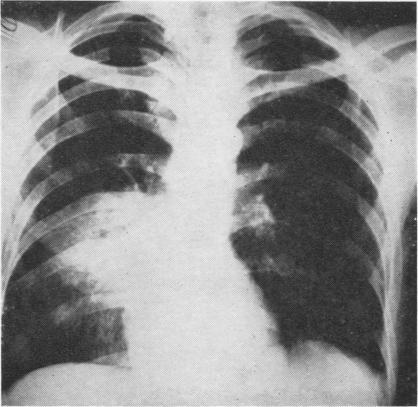

Thoracic actinomycosis.

Thorax. 1957 Jun;12(2):99-124. doi: 10.1136/thx.12.2.99.